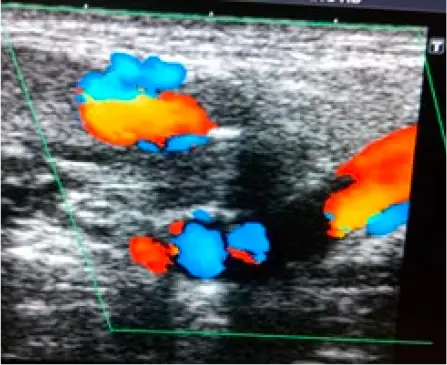

Colour doppler of left submandibular region revealing prominent vessels and biphasic, triphasic and venous pattern on spectral doppler, suggestive of Arterio-venous malformation.